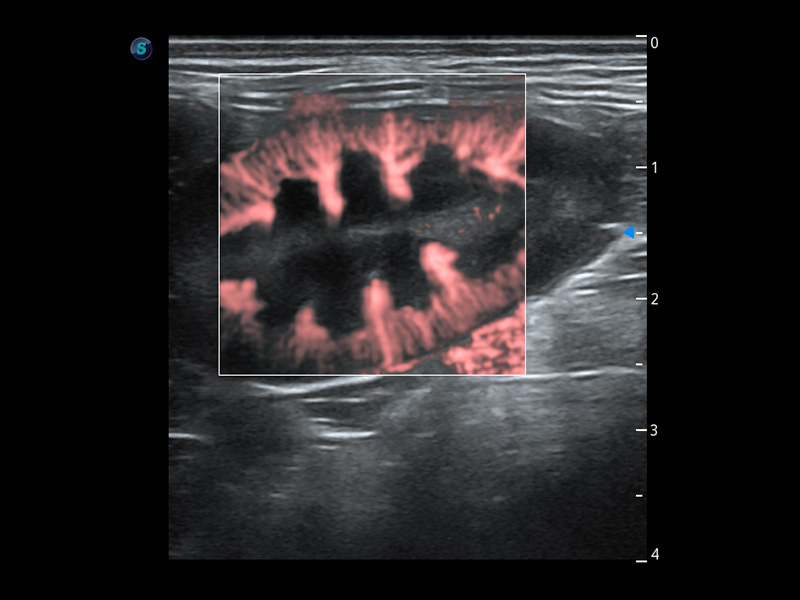

ProPet 60 作为一款高端台式动物超声设备,为动物医生的日常诊断提供了一系列贴合动物临床需求、解决临床实际问题的高级成像功能。凭借全系列高清探头,满足医生对腹部、心脏、生殖、浅表、肌骨等成像的所有需求,切实帮助您提升检查效率,提高诊断信心。

动物是人类最亲密的朋友和最值得信赖的伙伴。环球UG官网也一直致力于探索动物专用的超声影像解决方案。 全新推出的ProPet系列,是环球UG官网在动物超声影像智能化、专业化、精准化的一次跨越式革新。动物不能用言语来表述自己的不适,通过超声影像,ProPet系列搭建了动物医生与不同物种沟通的“桥梁”,为动物医生注入了“治愈之力”。